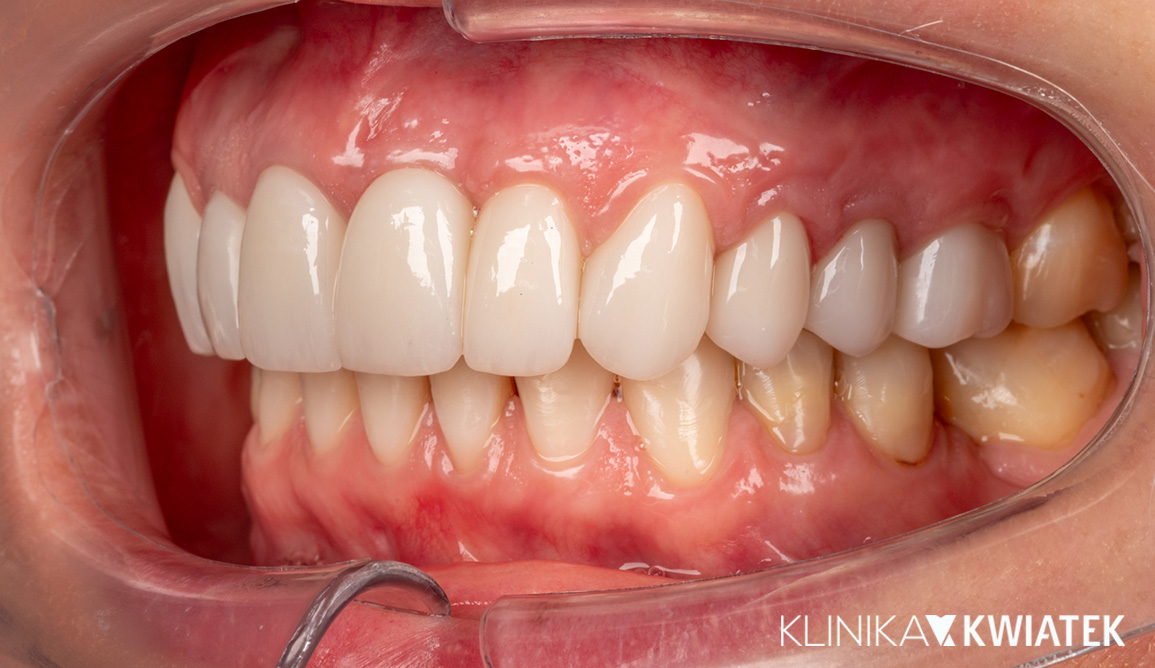

PO

Odbudowa estetyczna za pomocą koron, koron na implantach i licówek

Nasza Pacjentka marzyła o harmonijnym, jasnym uśmiechu – bez braków, asymetrii czy kompromisów estetycznych. Po zakończeniu leczenia ortodontycznego zdecydowała się na kompleksową metamorfozę: odbudowę brakujących zębów za pomocą koron na implantach, przeszczep dziąsła (FGG), wybielanie oraz bonding dolnych zębów techniką flow injection.

W trakcie leczenia korzystała także z fizjoterapii stomatologicznej, co pomogło zoptymalizować pracę stawów skroniowo-żuchwowych i mięśni żucia.

Efekt? Spójny, naturalny uśmiech, który nie tylko spełnił jej marzenie, ale też podkreślił rysy twarzy.